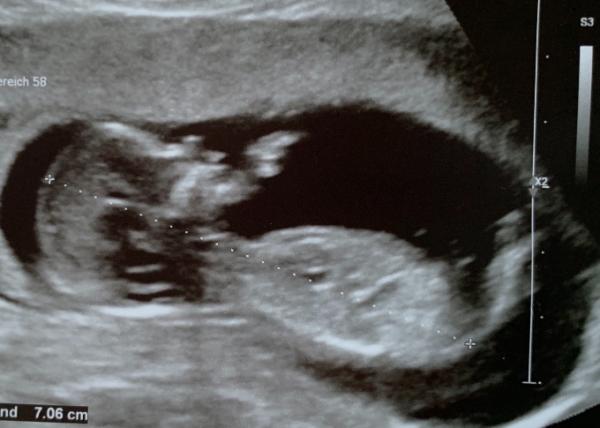

Hallo ihr Lieben, war heute beim Ersttrimester Screening und alles ist super Voraussichtlicher Geburtstermin ist der 10.03.2020 Zum Geschlecht wollte sich die Ärztin noch nicht äußern. Was es wird ist uns auch völlig egal, Hauptsache gesund. Aber neugierig sind wir schon Ich hänge euch mal ein Bild an, erkennt jemand was?

Bild zu Heute Ersttrimester Screening / Erkennt jemand was? - Forum für März - Mamis

Hallo wenn ich mal einen vorsichtigen Tipp abgeben darf würd ich eher sagen sieht aus wie ein Junge hab am 16.9 Termin hoffe auch so sehr das wir das Geschlecht erfahren (uns ist es auch egal was es wird hauptsache gesund aber neugierig ist man dann doch sehr)

Ein schönes Bild aber einen Tipp könnte ich darauf nicht abgeben